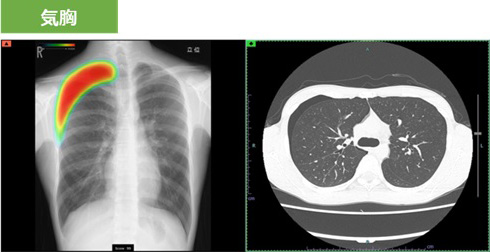

撮影した胸部レントゲン画像を自動解析して病変が疑われる領域を検出し、その部分をハイライトします。その領域を医師が再確認することで、見落し防止を支援します。

肺疾患の主要な画像所見となる「結節・腫瘤影」、「気胸」、「浸潤影」を検出することができます。